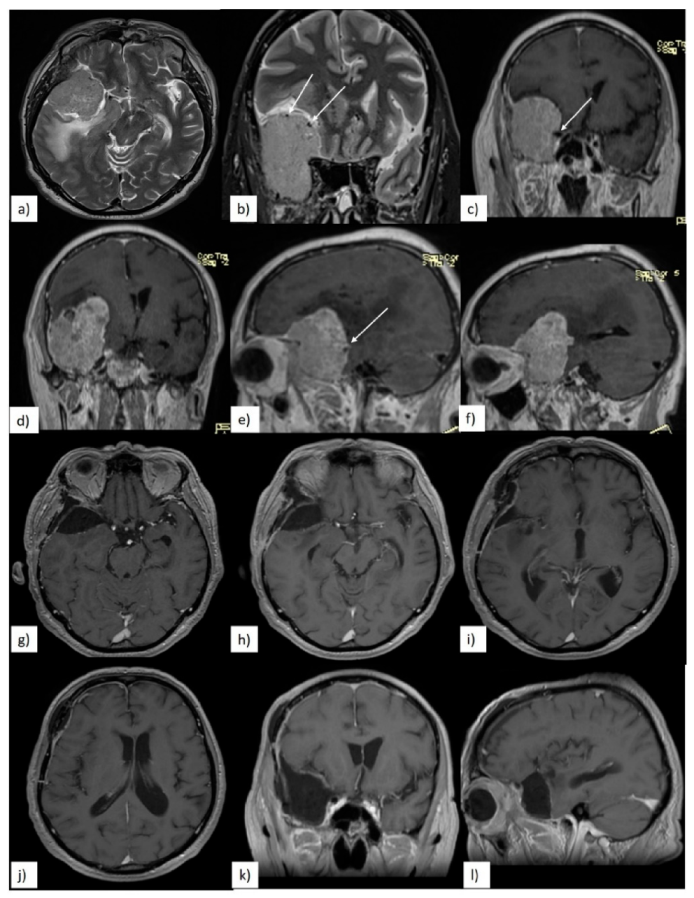

3.3. Quality of Resection

3.4. Postoperative Clinical Evolution and Follow-up

| Immediate Postoperative Clinical Evolution | Quality of Resection and Tumoral Progression | ||||

|---|---|---|---|---|---|

| Clinical Data | n (%) | Radiological Data | n (%) | ||

| unchanged | 14 (67%) | GTR | 14 (67%) | ||

| worsened | total | 7 (33%) | |||

| visual disfunctions | 4 (19%) | STR | 7 (33%) | ||

| motor deficits | 2 (9.5%) | location of residual tumor | total | 7 | |

| aphasia | 1 (4.7%) | cavernous sinus | 4 (57%) | ||

| long term clinical follow-up | ICA/MCA | 2 (29%) | |||

| improved | 17 (81%) | sphenoidal ridge | 1 (14%) | ||

| worsened | 2 (9.5%) | site of residual tumor which required surgical reintervention | cavernous sinus | 2 (9.5%) | |

| deaths | 2 (9.5%) | ||||

| surgical reintervention | 2 (9.5%) | ||||